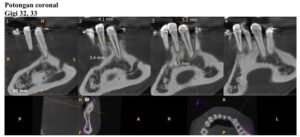

前回1月18日に歯石取りなどを終えており、歯茎の状態も特に悪化していることもなかったので、2月21日にレントゲン検査 (CBCT) 実施後、2月28日と3月28日に歯肉移植手術(下の歯左右2番と3番計4本に対し、左側と右側の2回に分けて行う)を実施することになりました。

・2026年2月21日撮影

・2025年9月13日撮影

・2022年10月1日撮影(約3年前)

レントゲン検査 (CBCT) の結果をもとに、歯肉移植手術を2回(2月28日と3月28日)に分けて実施しました。